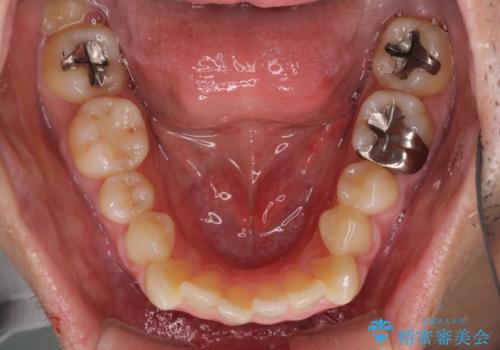

内側に転位した歯とボロボロのむし歯 インビザラインによる矯正治療とむし歯治療

- ボロボロのむし歯とデコボコの歯列を気にして来院された患者様です。

ボロボロとなっていた歯は抜歯が必要な状態でしたが、舌側転位している歯を移動させることで抜歯スペースを埋めることができるため、矯正治療により歯列を整えることとしました。

舌側転位の改善にインビザラインを用いるのはやや難易度が高くなりますが、前歯部のデコボコは軽度であったため、インビザラインによる矯正治療を行うこととしました。